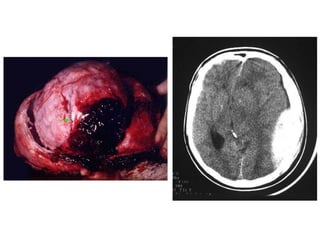

Tomografia Computadorizada do Crânio

• Alto grau de confiabilidade;

• Qualquer suspeita patológica envolvendo o encéfalo é indicativo de

TC;

Alterações visualizadas:

   Neoplasias;

   Lesões;

   Tumores

   Metástases;

   Hemorragia intracraniana;

   Aneurisma;

   Abscesso;

   Atrofia cerebral;

   Alterações pós-traumáticas;

   Alterações congênitas.